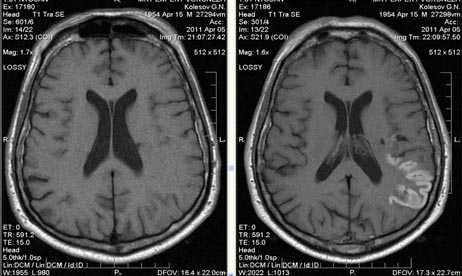

Характерным проявлением ДЭП на МР-томограммах является наличие множественных очагов глиоза.

В белом веществе левой лобной и обеих теменных долей, преимущественно субкортикально, выявлены множественные мелкие очаги хронической ишемии (большинство локализованных в бассейне правой средней мозговой артерии).

Проявлением хронической ишемии является также развитие выраженных дистрофических изменений белого вещества паравентрикулярной локализации - лейкоареоз.

Выраженные дистрофические изменения белого вещества паравентрикулярной локализации - лейкоареоз.

Сочетание мультифокальных очаговых изменений с диффузной кортикальной церебральной атрофией.